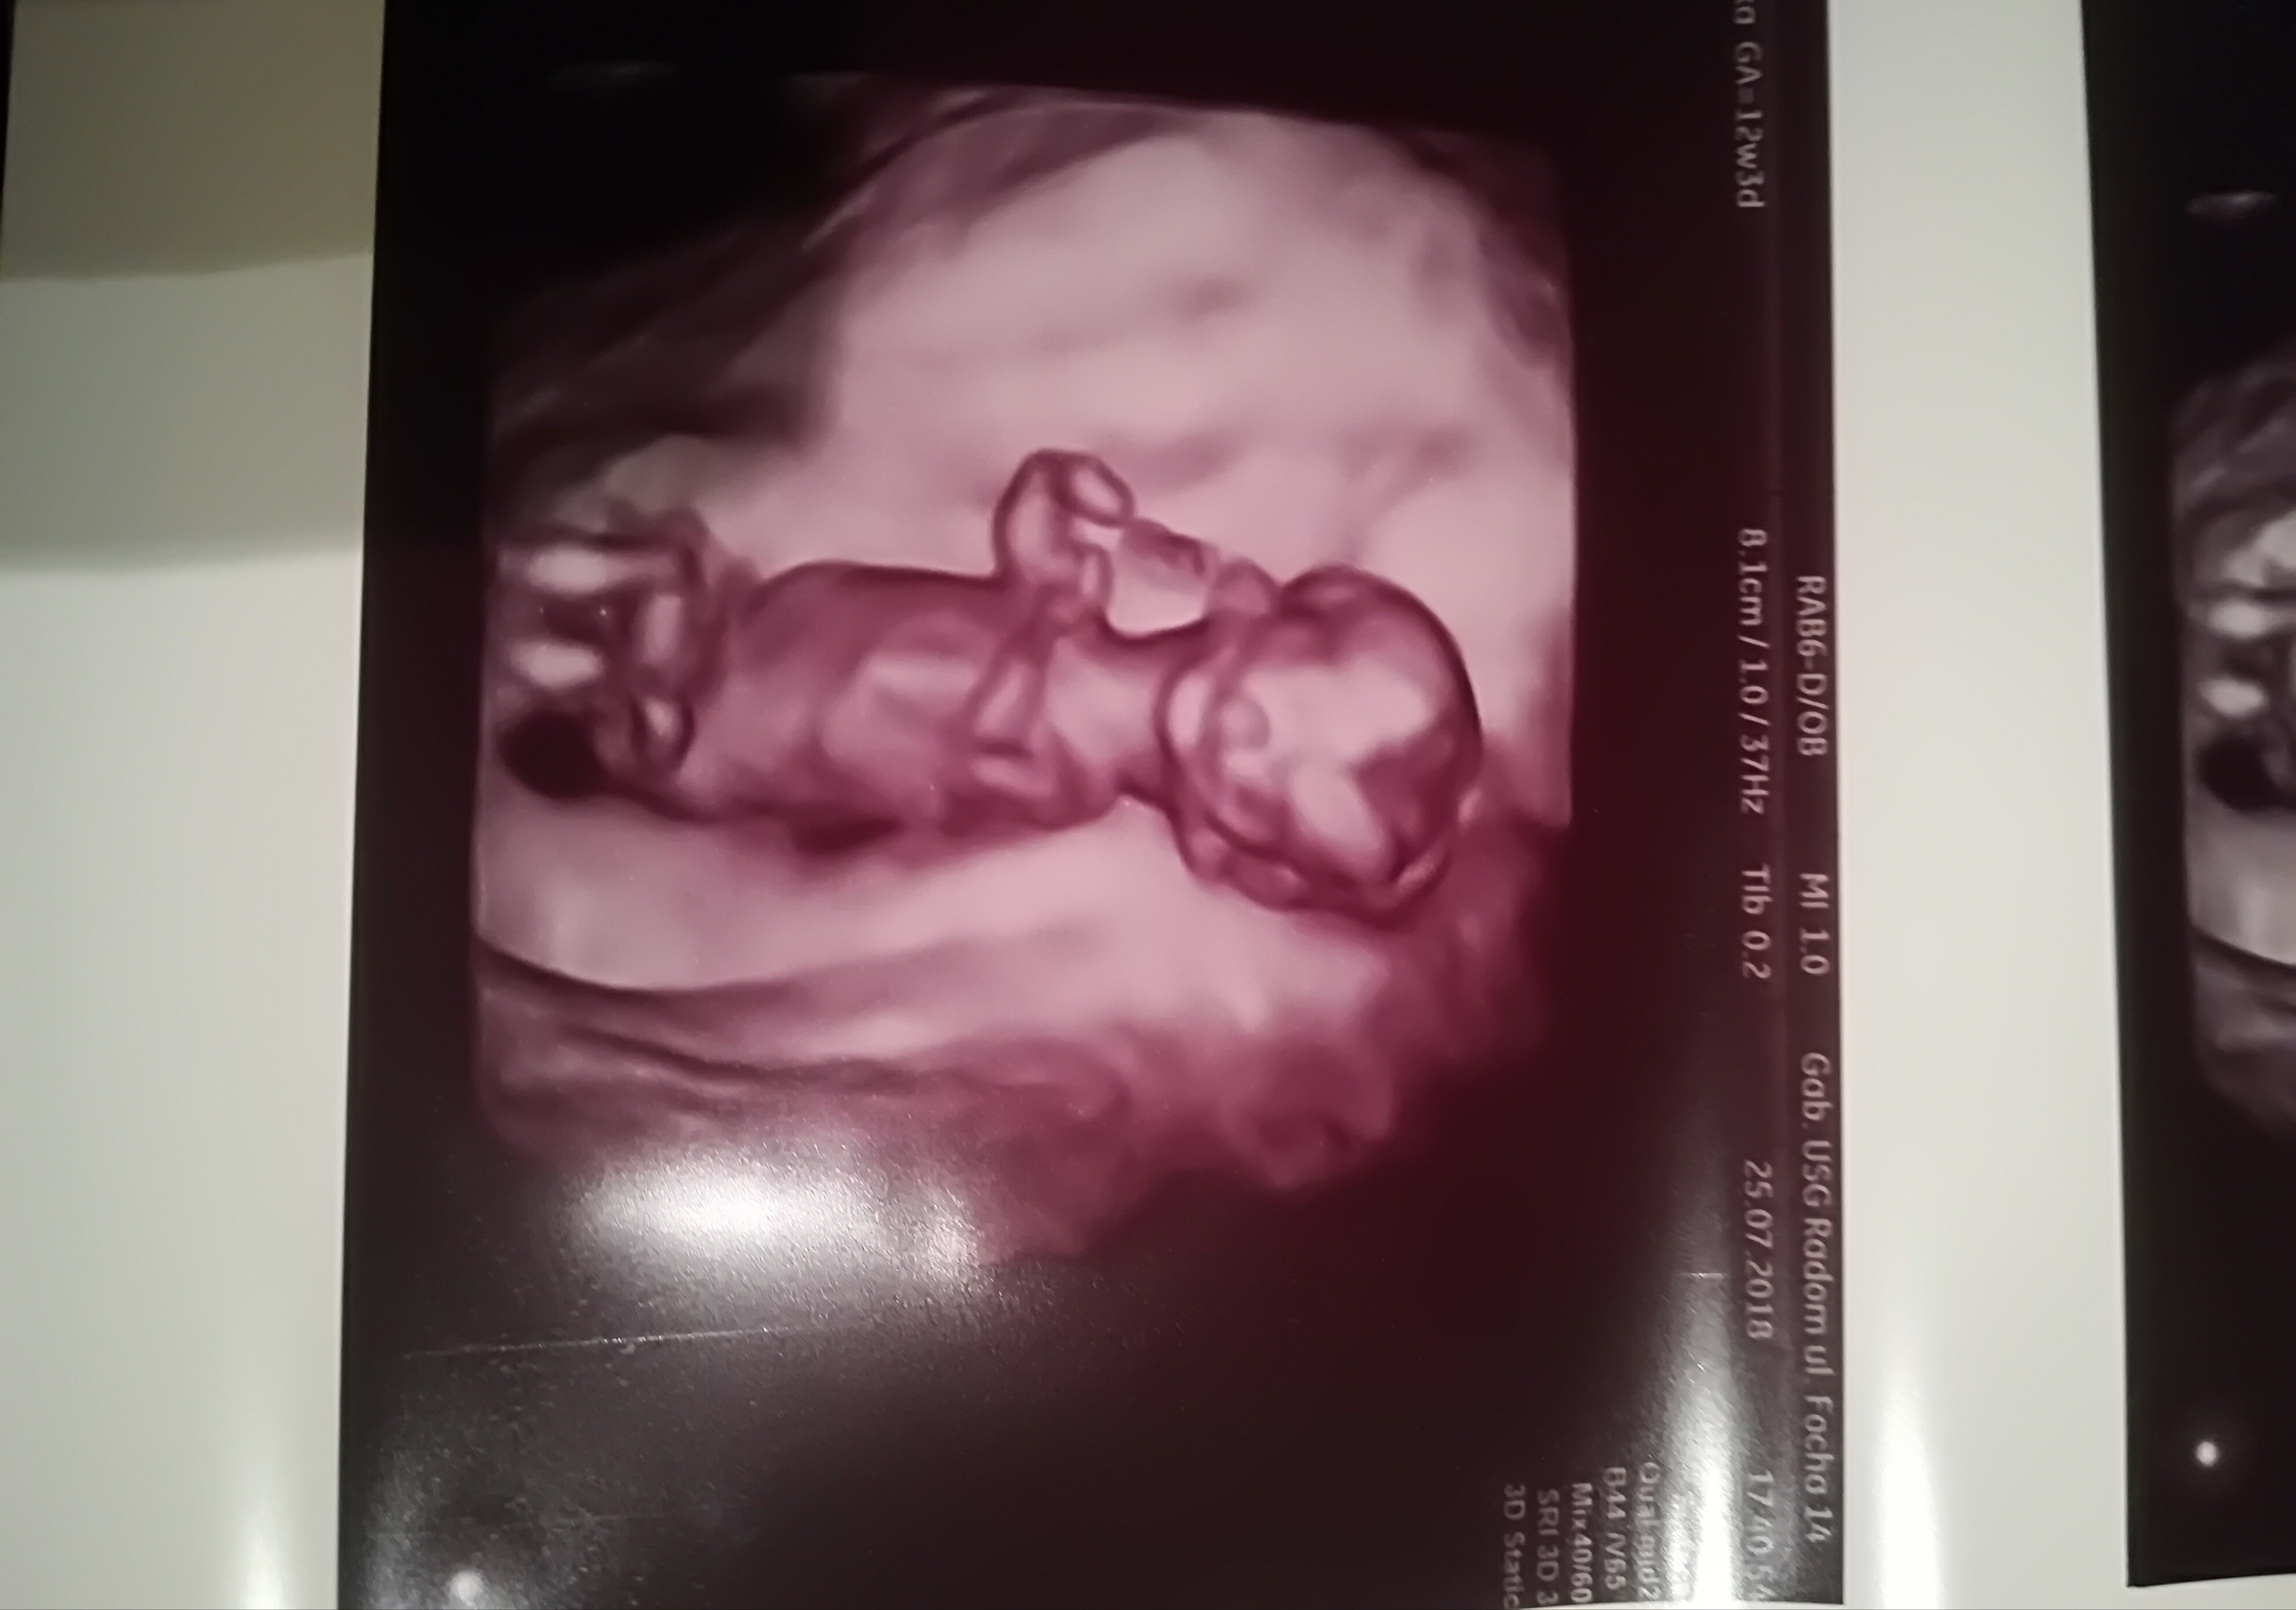

Dziękuję wszystkim za gratulacje. Moje dziecko to uroczy kosmita;-) dołączam xdjecieAnita to jeszcze poprosimy zdjęcia małego człowieka ;-)